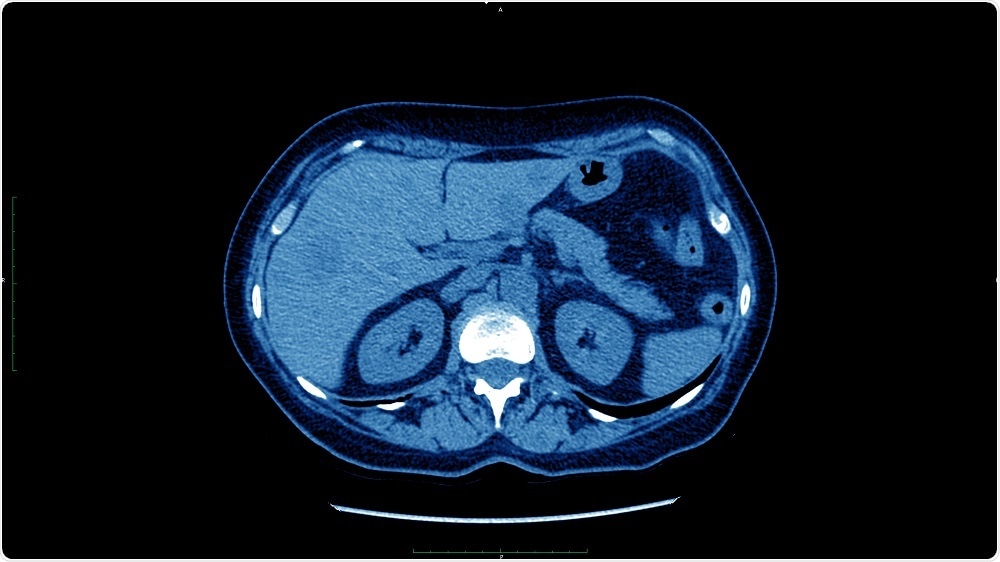

Credit: dade72/Shutterstock.com

Credit: dade72/Shutterstock.com